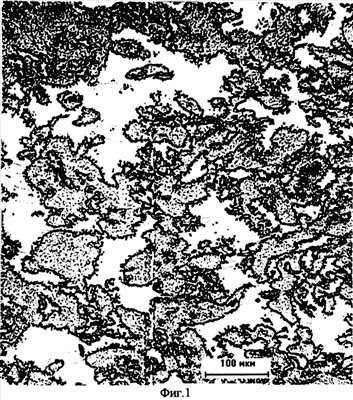

На фиг.1 представлен снимок структуры имплантата, сделанный под микроскопом. Отчетливо видна трехмерная сеть пространства пустот и узлы полимерной матрицы.

Согласно определению структура заявляемого имплантата имеет объемную долю пространства пустот 15-40%, удельную поверхность пространства пустот 0,25-0,55 мкм2/мкм3, среднее расстояние между пустотами в объеме 25-50 мкм и среднюю объемную хорду 8-25 мкм.